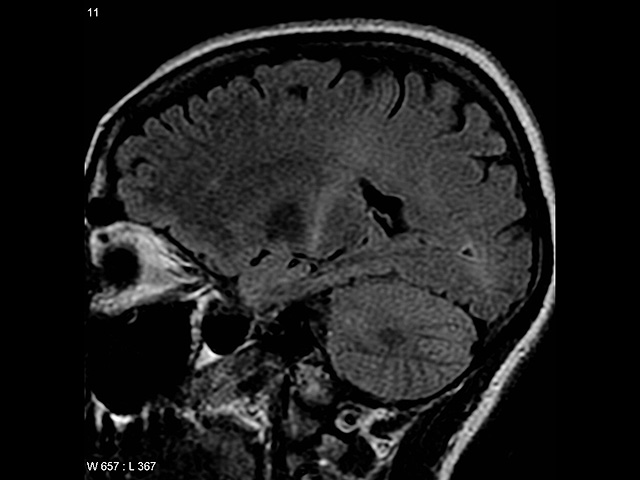

Wikipedia.org. Фото: Frank Gaillard